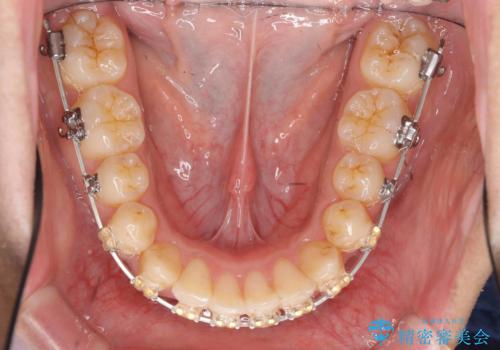

- 矯正装置

- 審美装置

- 治療期間

- 1年6ヶ月

- 治療回数

- 10-30回